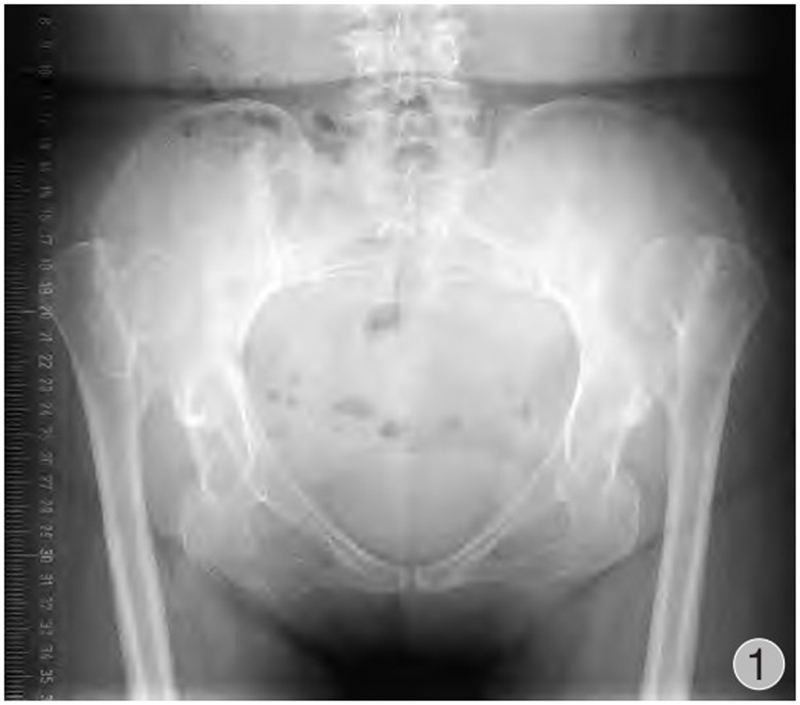

由于股骨头半脱位或脱位,发育中的真性髋臼缺乏应力刺激未能正常生长发育,骨性髋臼形成通常较小,多呈三角形,被软组织所覆盖,部分病例会有骨性覆盖以及骨性解剖标志丧失等(图1~3)。发育不良的髋臼往往较浅且前倾增大,前壁变薄,骨量不足,前后径减小,可有上方和(或)前方节段性缺损。根据是否存在假臼,有学者将Crowe Ⅳ型进一步分为Ⅳa(无假臼)和Ⅳb(有假臼),并提出假臼的存在是影响THA脱位高度和转子下截骨术应用的重要因素,HARTO等发现无假臼的高脱位DDH患者THA术后假体存留率不及有假臼形成患者,并且假臼的存在与否影响近端股骨的应力传导并可能与近端股骨形态有关,因此包含形态分类的术前规划是有必要的。如何寻找真臼的位置以及髋臼杯的安放是手术成功的关键。

图1 术前骨盆正位DR:双侧CROWE Ⅳ型DDH,股骨头脱位高度>股骨头高度的100%。双侧均无假臼形成;真臼未能正常发育,髋臼浅小;股骨头小、不规则;股骨颈短,颈干角减小,偏心距减小,股骨近端骨皮质变薄,髓腔窄小变直,呈柱状,髓腔峡部位置相比正常股骨较高

Crowe Ⅳ DDH股骨近端大小形态都与正常不同,股骨畸形可因脱位程度的增加而增加,有患者因股骨或骨盆矫形手术病史使得解剖更复杂。具体表现为股骨头小、不规则、失去圆形状态,股骨头软骨表面磨损严重,因假臼的反复刺激,股骨头周围可产生骨赘。股骨头位置高(相对于小转子),大转子-股骨头距离增大,股骨颈短,前倾增大,大转子后置,Sugano等发现DDH患者股骨颈前倾角平均增加10°~14°,但增大程度与脱位程度无关。此外,颈干角增大,偏心距减小,股骨前弓增大,近端骨皮质变薄,骨质脆性较大,弹性降低,远端股骨明显内旋。近端髓腔窄小变直,多呈柱状(烟囱型髓腔),髓腔峡部位置相比正常股骨较高,近端髓腔和峡部内径都较正常股骨小,前后径大于内外侧径(图1)。髓腔形态异常可随脱位程度增加而增加,小转子和峡部之间的骨干内产生扭转并与干骺端扭转异常无关。为此,需在术前通过影像学方法预测股骨髓腔直径、测定股骨前倾角、测定股骨偏心距。